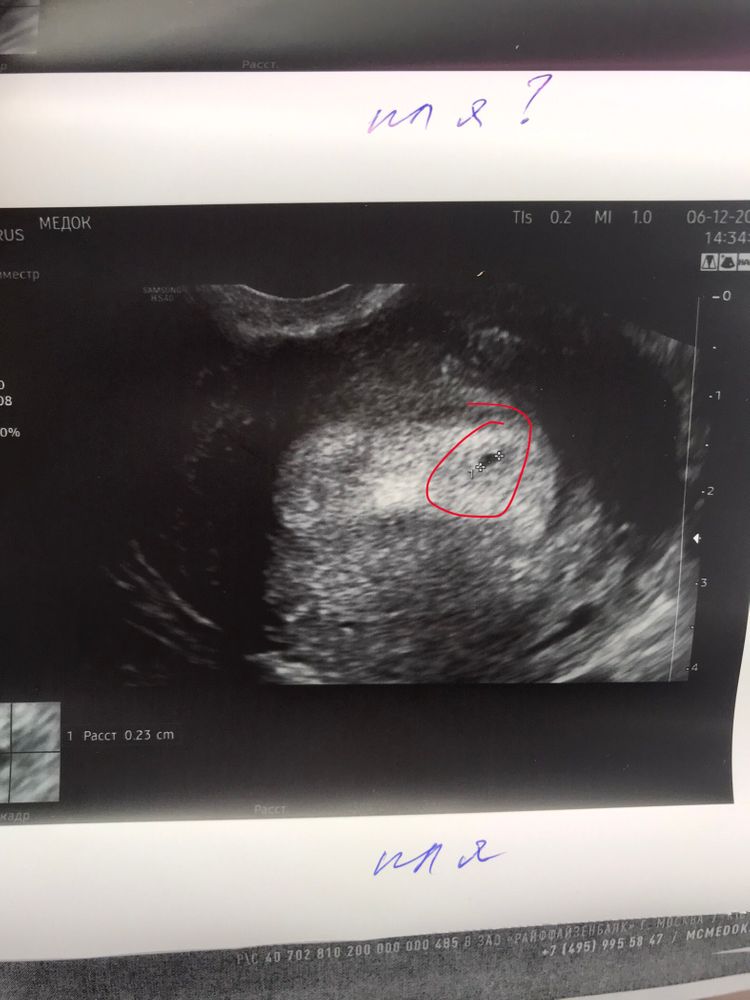

Всем доброго времени суток, дорогие девушки. Сегодня сходила на УЗИ - по моим подсчетам 5 день 5 акушерской недели(овуляция была 17 ноября, ПА 19). Фото в ответах! 😇 Все тесты уже давно с двумя полосками, сегодня хотела убедиться, что тело в матке, все в порядке. Неожиданно было обнаружено второе плодное яйцо! Подскажите, пожалуйста, у кого двойня, у вас есть так примерно выглядело? Бывало такое, что ставили то же самое, но в итоге был один малыш?) один детёныш 1,9 мм(который под вопросом), второй 2,3 мм - который точно. заранее огромное спасибо за ответы! 😘